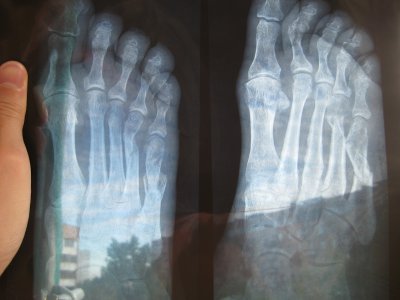

Здравствуйте, у меня три месяца назад был перелом со смещением отломков плюсневых костей, а также ладьевидной и кубовидной, было наложено вытяжение, гипс сняли месяц назад, отек до сих пор не проходит, лечили ультразвуком и магнитотерапией, что ещё можно сделать?Нога не влезает ни в какие ботинки!!!